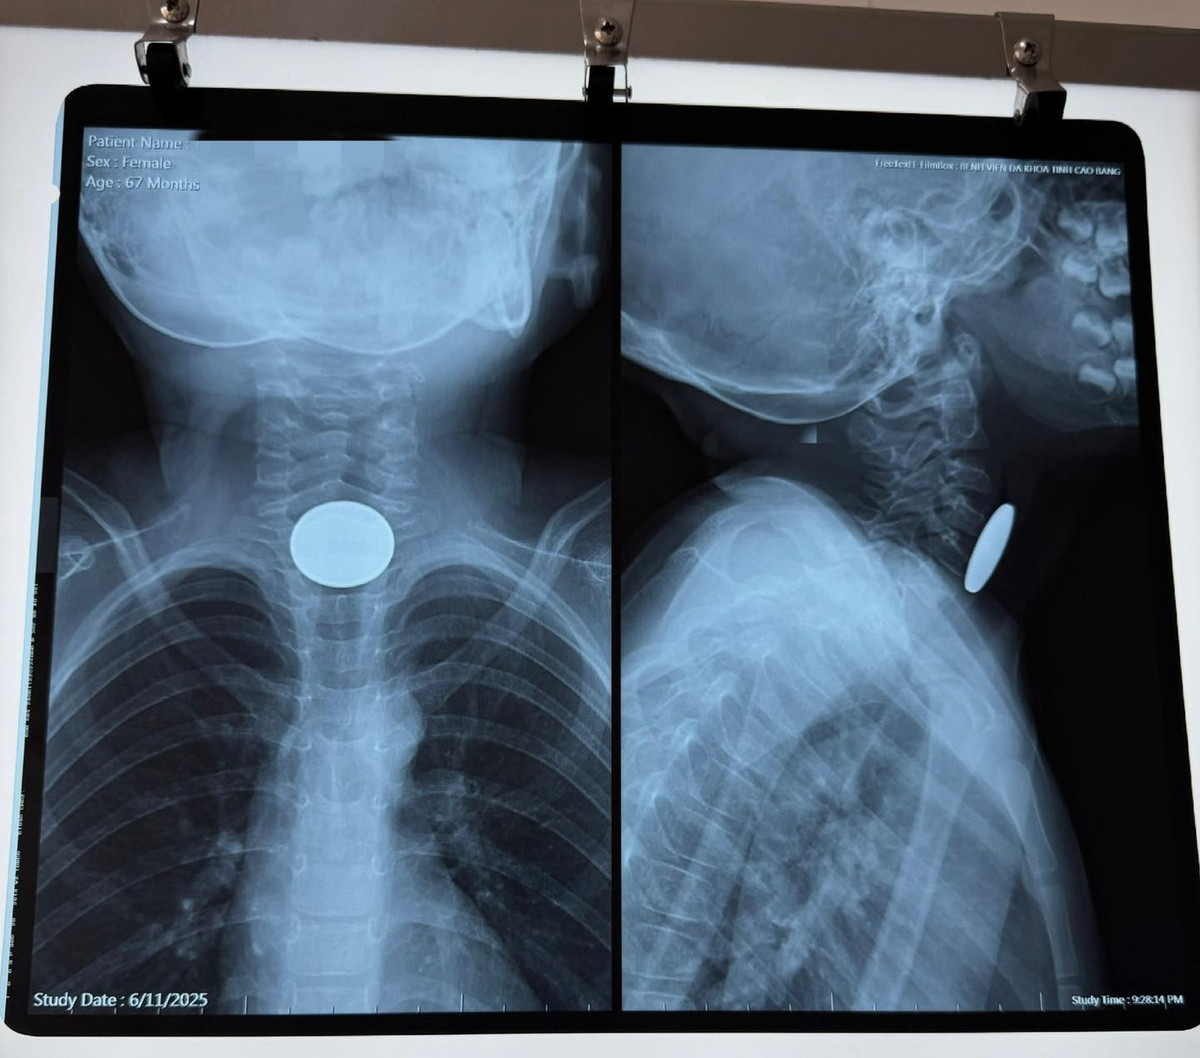

Đồng xu 2,5 cm mắc kẹt trong thực quản bé gái hơn 5 tuổi

Phụ huynh cần đặc biệt lưu ý không để trẻ chơi với các vật nhỏ, dễ nuốt như đồng xu, pin cúc áo, đồ lắp ráp nhỏ…

Ngày 11/6, Bệnh viện Đa khoa tỉnh Cao Bằng vừa tiếp nhận và xử trí thành công một trường hợp trẻ nhỏ nuốt dị vật nguy hiểm. Bệnh nhi là bé gái hơn 5 tuổi, trú tại thành phố Cao Bằng, được người nhà đưa đến bệnh viện trong tình trạng không nuốt được, buồn nôn nhưng không nôn được, khó thở sau khi chơi một mình tại nhà.

nuot-dong-cu.jpg

Hình ảnh dị vật đồng xu trên phim chụp - Ảnh BVCC